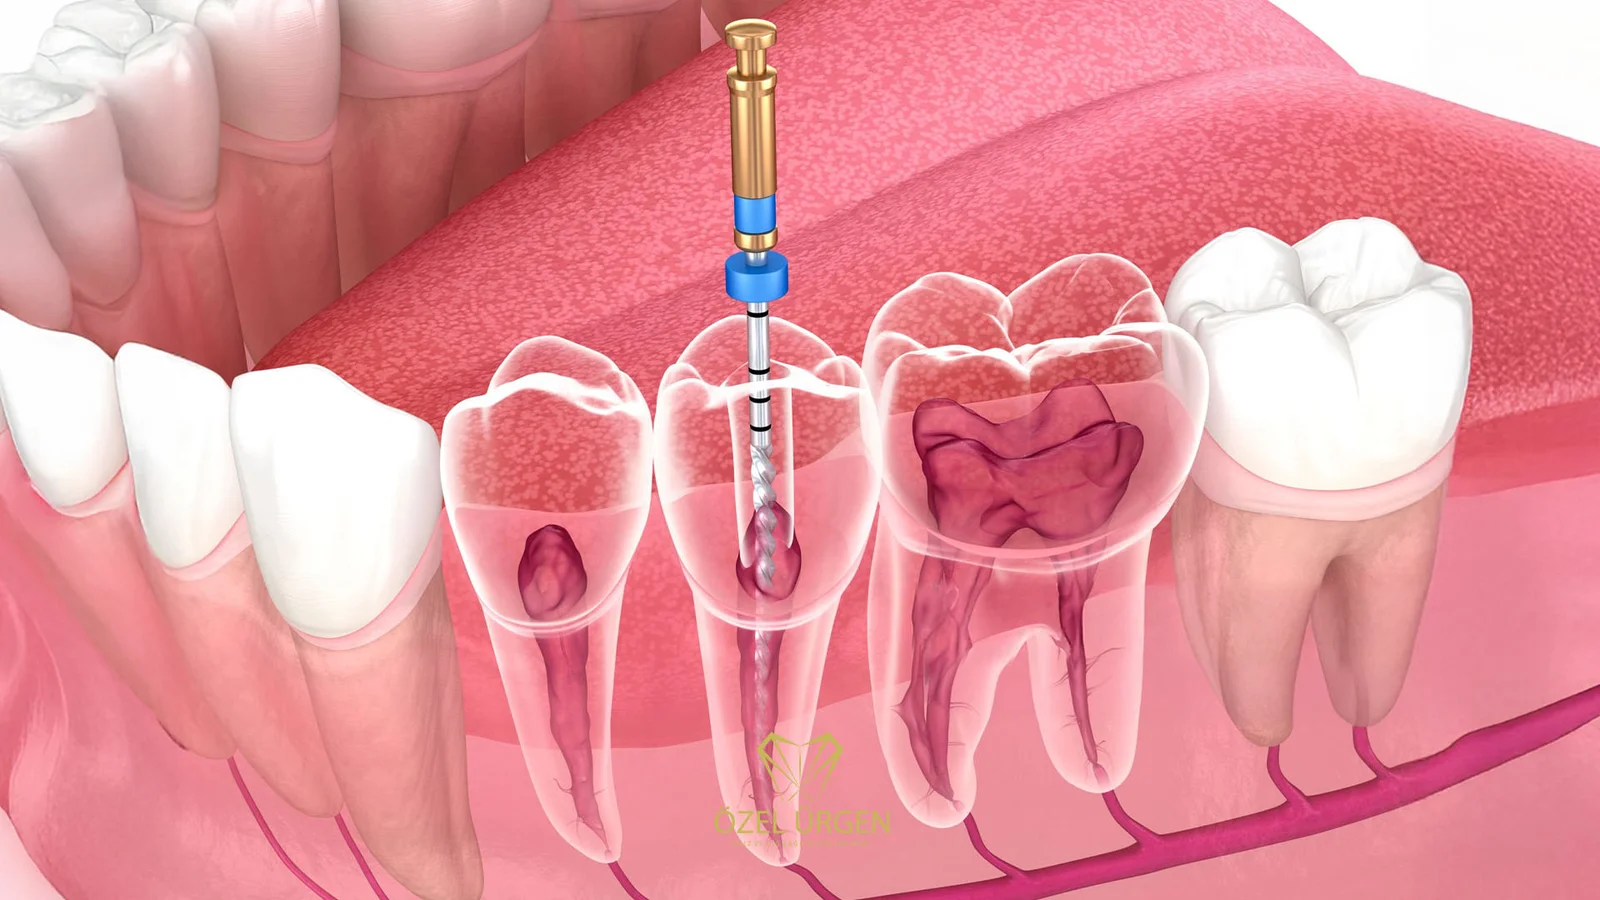

Kanal Tedavisi Nasıl Yapılır Kanal tedavisi nasıl yapılır, dişinde ağrı, hassasiyet veya enfeksiyon yaşayan hastaların en çok merak ettiği konuların başında gelmektedir ve bu tedavinin yalnızca yüzeysel bir işlem olmadığı özellikle bilinmelidir çünkü kanal tedavisi, dişin en derin yapısına kadar…

Kanal tedavisi Antakya Kanal tedavisi Antakya bölgesinde dişini çekmeden korumak isteyen hastalar için uygulanan, enfekte veya geri dönüşü olmayan şekilde hasar görmüş pulpa dokusunun tamamen temizlenerek dişin ağız içinde fonksiyonel şekilde tutulmasını sağlayan ileri düzey bir endodontik tedavidir ve bu…